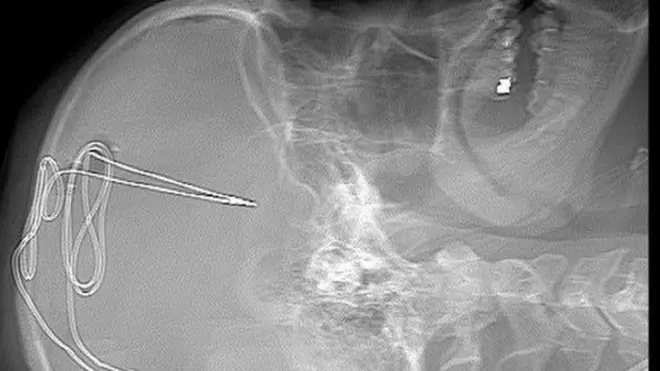

El tratamiento con ECP consiste en implantar un dispositivo eléctrico directamente en el cerebro del paciente para estimular los circuitos donde haya una actividad anormal o un "cableado" disfuncional, y ayudar a reajustarlos. La ECP se describe con frecuencia como un tipo de "marcapasos" para el cerebro.

Los electrodos se insertan en una región específica del cerebro para recalibrar la actividad en esa área utilizando impulsos eléctricos y para reducir la necesidad de consumir alcohol.

Estos electrodos son controlados por un dispositivo similar a un marcapasos que se coloca debajo de la piel del pecho.

Plummer fue el primer paciente del ensayo. Se sometió a una cirugía experimental hace poco más de un año.

Plummer dice que la peor parte fue el ruido y las vibraciones de los cirujanos perforando su cráneo para implantarle los electrodos.

"Era un taladro grande que te hace un hueco del tamaño de una moneda de 25 céntimos en ambos lados del cráneo. No fue doloroso, pero sí molesto", recuerda.